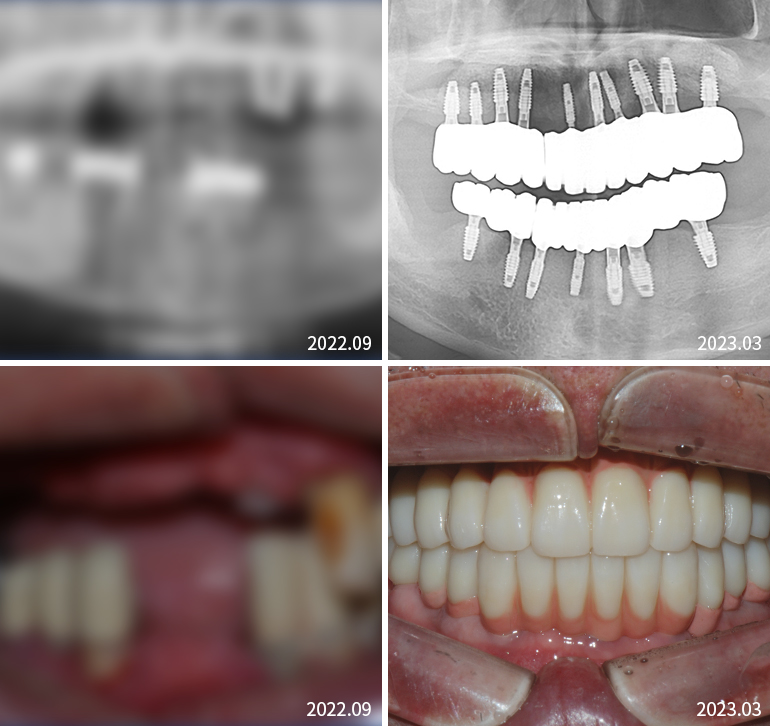

전체임플란트